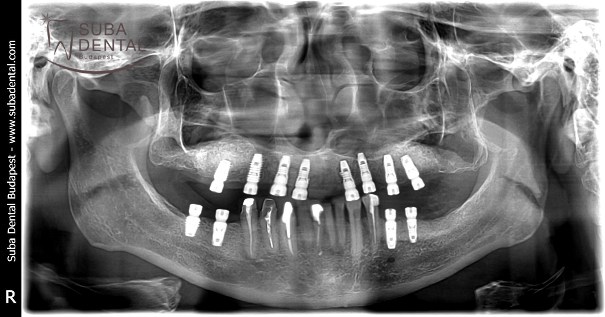

Panoramic radiograph of the lower and upper bar